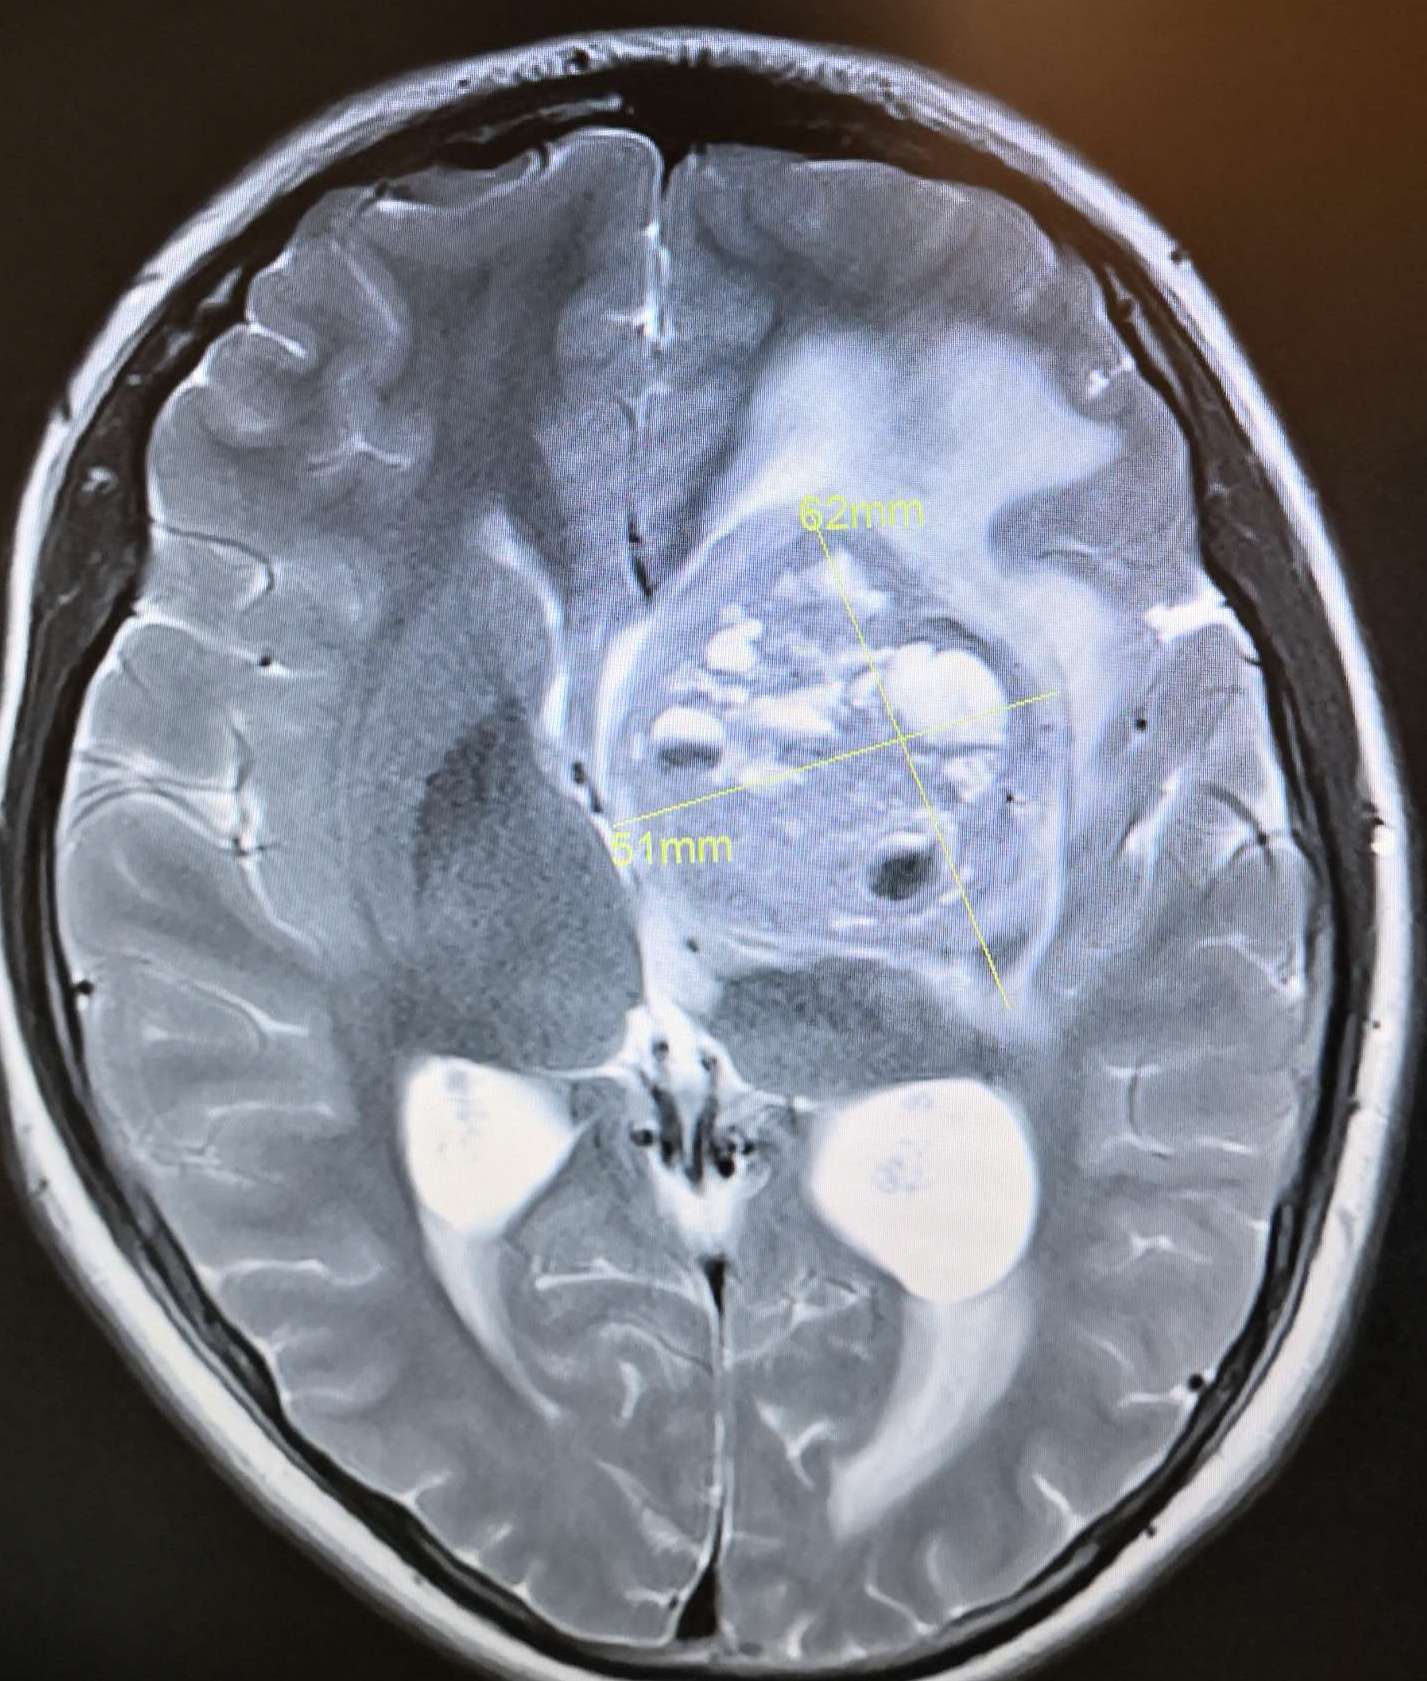

术前头颅MRI T2显示:左侧基底节巨大占位病灶(61*62mm),呈高、等、低混杂信号,脑室受压,中线移位明显。